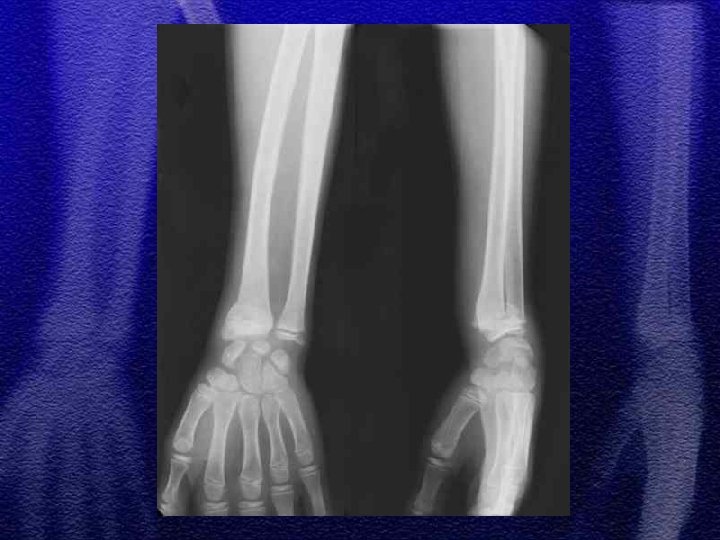

§ Złamania przynasad § Złuszczenia dalszej nasady kości promieniowej to najczęstszy uraz chrząstki nasadowej u dzieci § Najczęstsze złuszczenia typ I i II § Typ III IV i V występują sporadycznie, są obarczone możliwością wywołania zaburzeń wzrostu kości (zniekształcenia pseudo-Madelunga)

§ Nastawienia zachowawcze u dzieci powinny być wykonywane w znieczuleniu ogólnym § Wyjątek stanowią złamania z niewielkim przemieszczeniem